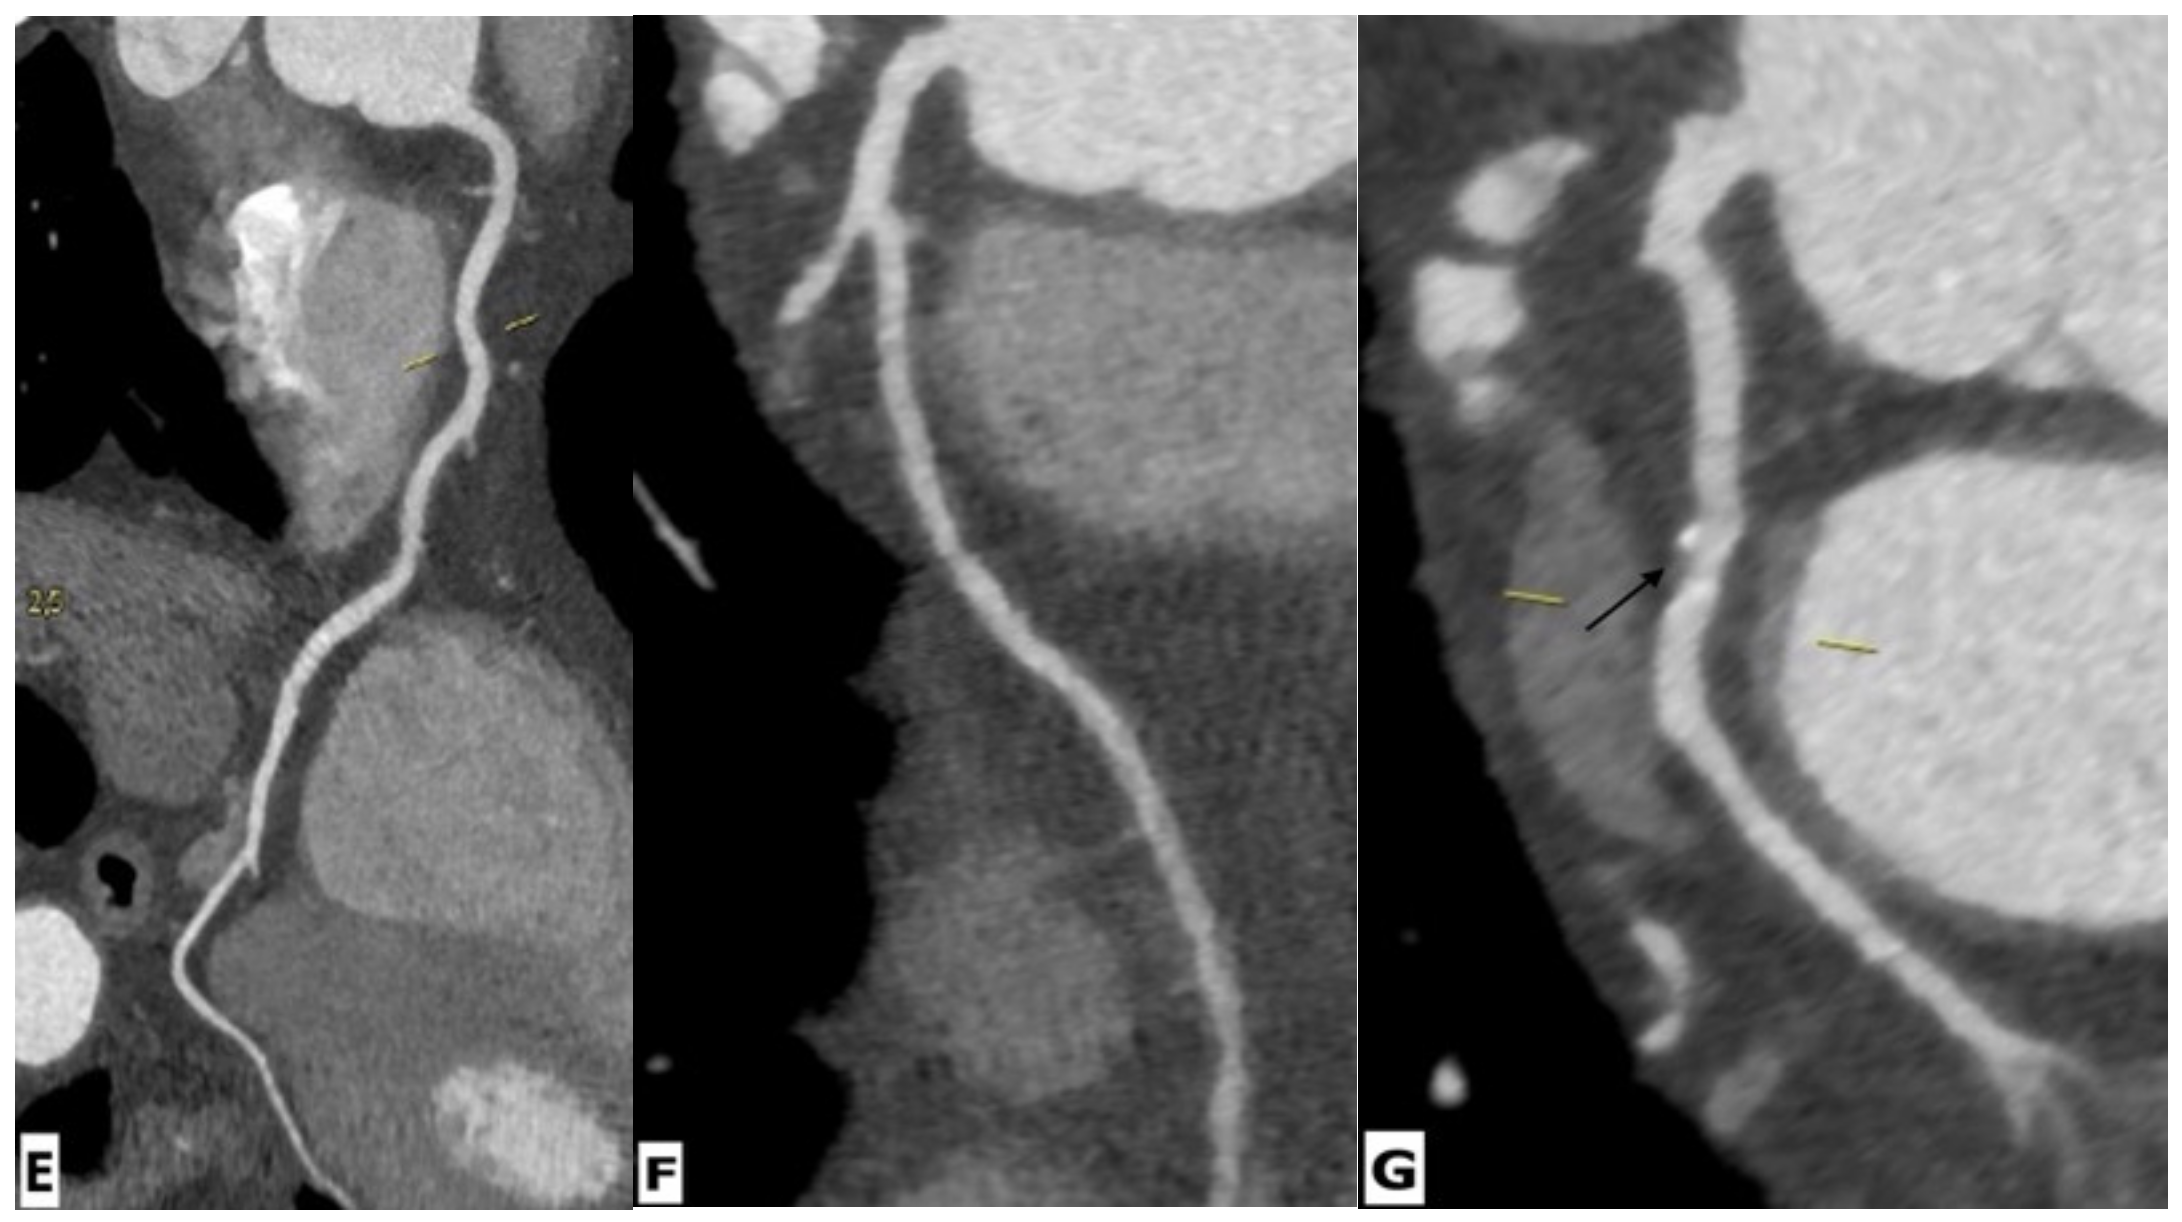

| Vasculitis | Gouny et al. | Case series | 3 | CTA | First case: a saccular aneurysm of the aorta whose neck was situated 3 cm proximal to the renal arteries and associated with a left lateral aortic hematoma; Second case: a fusiform aneurysm with a retroaortic extravasation suggesting chronic rupture and thickening of the anterior aspect of the aneurysmal wall; Third case: a fusiform aneurysm of the aorta extending to the common iliac arteries with its neck located 3 cm distal from the renal arteries. |

| Sellami et al. | Case report | 1 | CTA | Early CT finding consisted of a slight-enhancing periaortic soft-tissue, while the aorta remained of normal size. Within two weeks, infection progressed to an infected aneurysm. | |